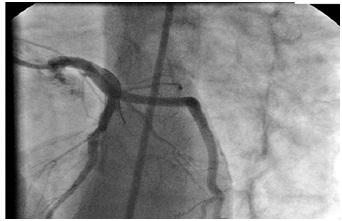

Coronary Aneurysm and Myocardial Infarction in Young Adult Secondary to Undiagnosed Childhood Kawasaki Disease

Didem Ay